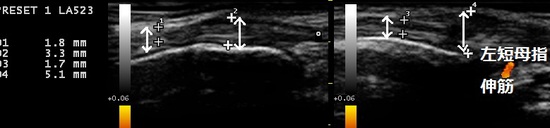

川越市 主婦 親指の痛み ドケルバン病(狭窄性腱鞘炎)

右親指の付け根 左親指の付け根

親指を曲げて小指側に押すと激痛が走ります。超音波画像で左右の親指を伸ばす腱の一部が

左右とも太く腫れていました(上画像の矢印の比較)。